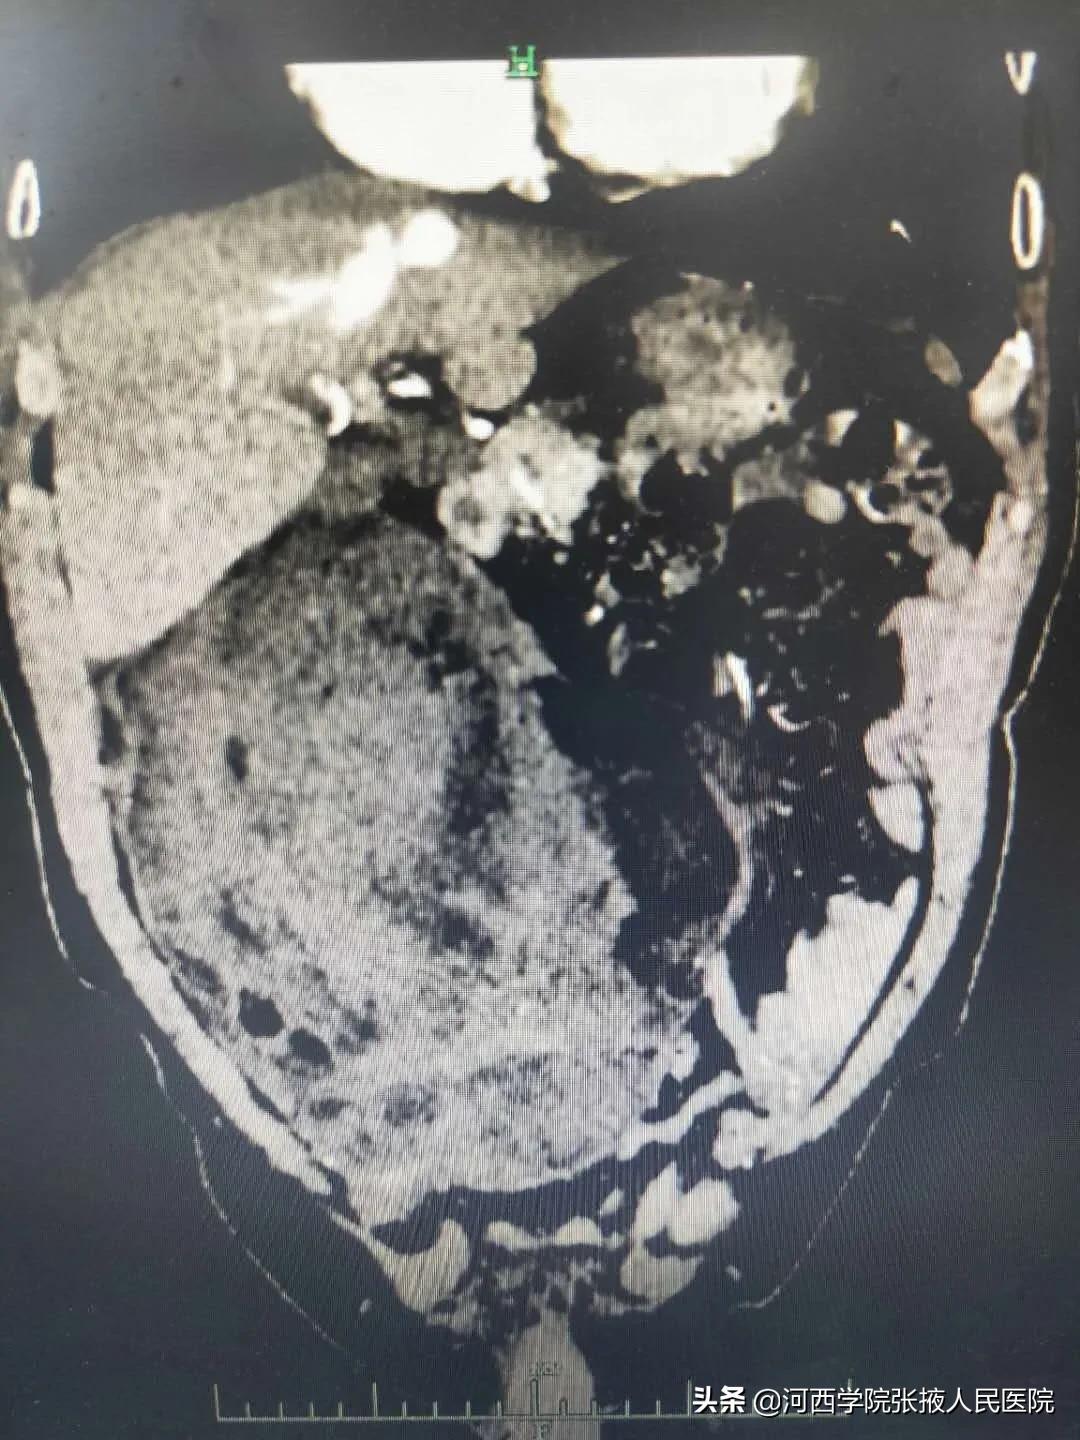

腹部CT检查示:右侧腹膜前间隙见巨大不规则混杂密度肿块影,病灶上缘起自十二指肠降部平面,下缘达膀胱上方,病灶边缘可见包膜,供血动脉来自右侧腹壁下动脉。提示:右侧腹膜前间隙巨大占位性病变,考虑脂肪肉瘤。

经反复阅片后积极术前准备,于2月25日,普外二科团队在全麻下为患者行腹膜后巨大肿瘤切除术,术中患者血压高至200/120mmHg,历经2个小时手术,79岁的张大爷在我院“甩”掉了腹内重达4公斤、直径约20cm的巨大肿瘤,那一刻生命重新起航。